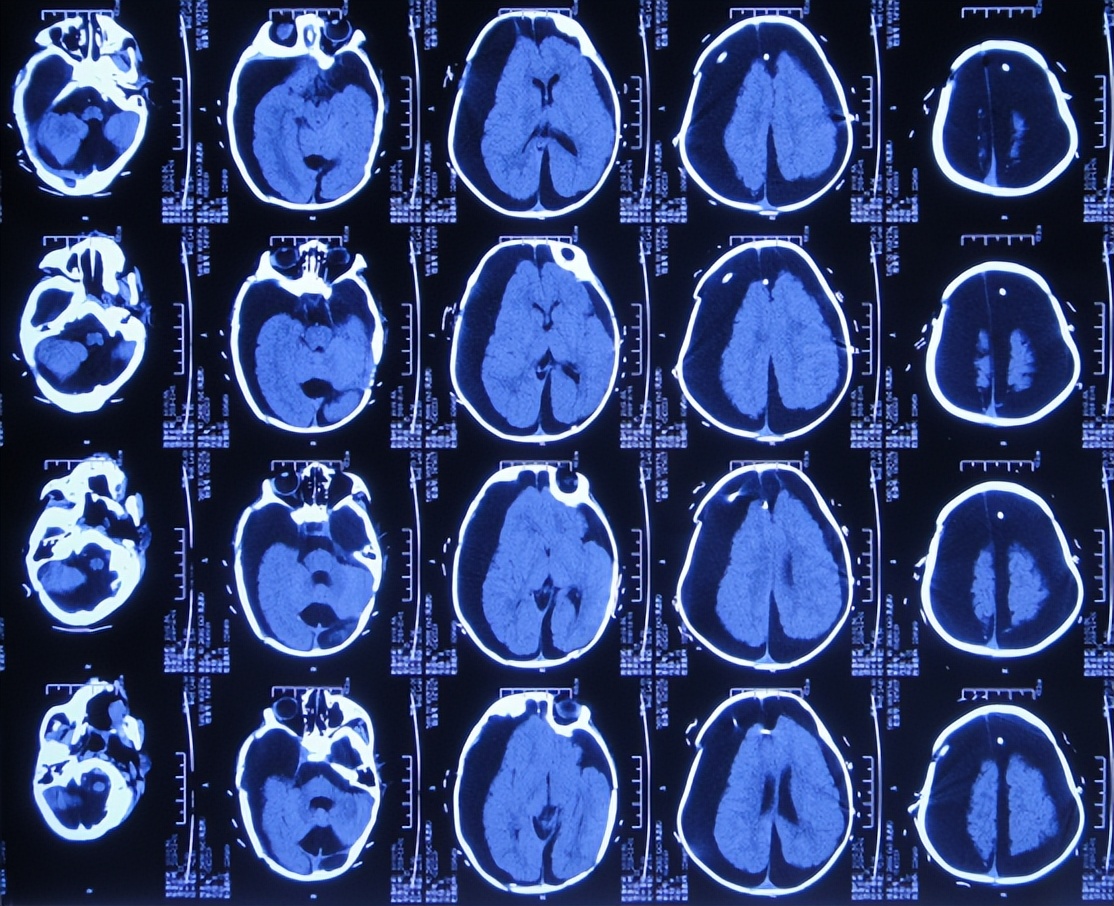

但调压3天后即2019年3月19日,因仍未见改善,且患儿病情加重致变得不能哭,家属带着患儿第2次住入第4家医院,头颅CT示硬膜下积液,脑积水( 图-20 );给予甘露醇对症脱水降颅压治疗。

图-20: 2019年3月19日头颅CT

治疗2天后即2019年3月21日,仍未见改善,查头颅CT示脑室重度扩张( 图-21 ),且仍持续发热38.5度。

图-21: 2019年3月21日头颅CT